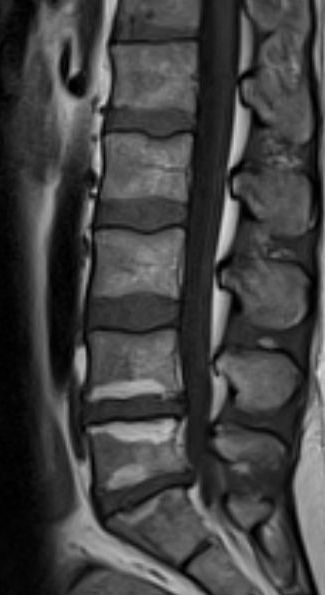

Modic is an appearance on an MRI scan first described by Michael Modic  specialist in spinal radiology from the USA. He described 3 types of Modic.

MRI scanning is complex there are 2 common types of scan - 'T1' and 'T2' weighted images you do not need to know the details of these

Modic change is bright on T2 (the right picture) and dark on T1(the left picture)

Modic Type 1 is related closely to severe back pain and Modic Type 2 in many instance also.  Modic Type 3 is usually pain free.

These modic changes occur in the bone adjacent to the disc, they reflect a reaction to the infection in the disc.

You need an MRI scan. The MRI scan has to be interpreted by someone trained too identify 'Modic changes'. In addition you need to be in the hands of a clinician who recognises the clinical syndrome of Modic-related back pain described above, i.e. someone who can differentiate your pattern of pain from the normal backaches that affect us all.

That is to say it is like many diagnoses in medicine. You need a specialist who understands the different causes of back pain and can differentiate one from the other. That specialist then requires a particular test; in this instance an MRI scan. It is not possible to detect by MRI scanning alone or indeed by the clinical history whether you have Modic-related back pain and are a suitable candidate for MAST. The only way of doing this is to have both the specialist opinion and the MRI scan.